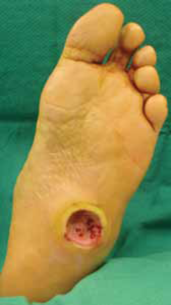

糖尿病会造成体内各部位的血管和神经受损,包括眼睛和四肢。糖尿病患者因为血液循环差,神经也可能受损,患上足部和眼睛疾病的风险也随之增高。

请根据医生建议定期做视力检验和下肢血管、神经的检查,万一眼睛出现问题,可以及早发现与治疗。另外,请注意脚部的护理如果脚部出现问题,你便能很快地发现,并及早采取措施,预防病情恶化。